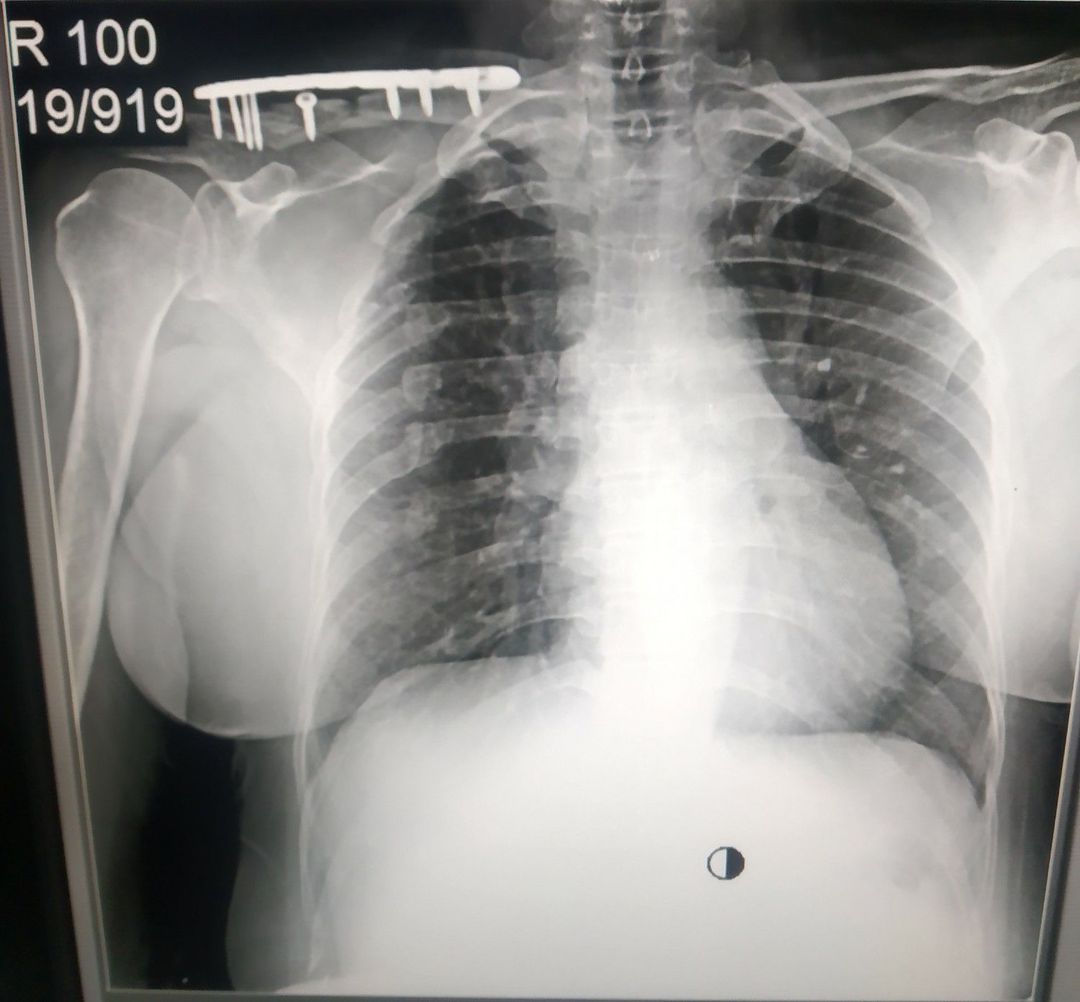

The case with clavicle fracture..... 😵

Fracture

Clavicle

Claviclefracture